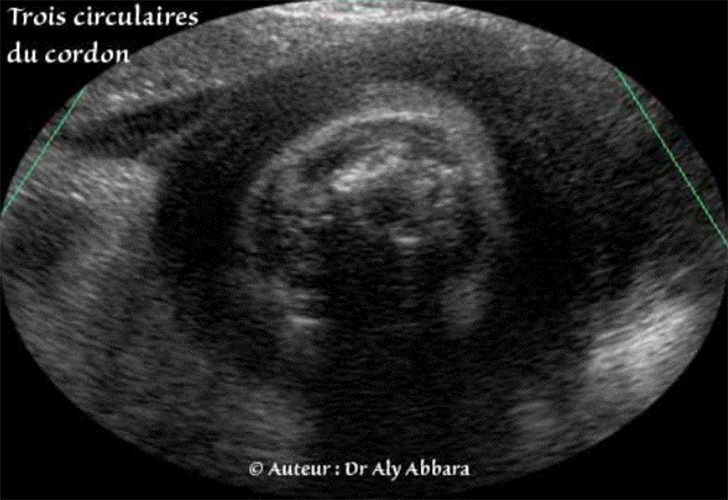

Cordon ombilical - Triple circulaires - 39 SA - Echographie

Triple circulaire cervicale du cordon ombilical

(Fœtus âgé de 39 SA).

• Série d'images échographiques permettant de suspecter la présence de trois circulaires du cordon ombilical autour du cou fœtal.

Les coupes échographiques transversales du cou fœtal. avec l'activation du Doppler couleur évoquent la présence du multiple vaisseaux sanguins d'origine funiculaire, donc plus d'une seule circulaire, puis la coupe échographique sagittale médiane du cou, permettait de suspecter la présence de trois circulaires du cordon ombilical.

• A la naissance, la présence de trois circulaires cervicales serrées du cordon fut confirmée.